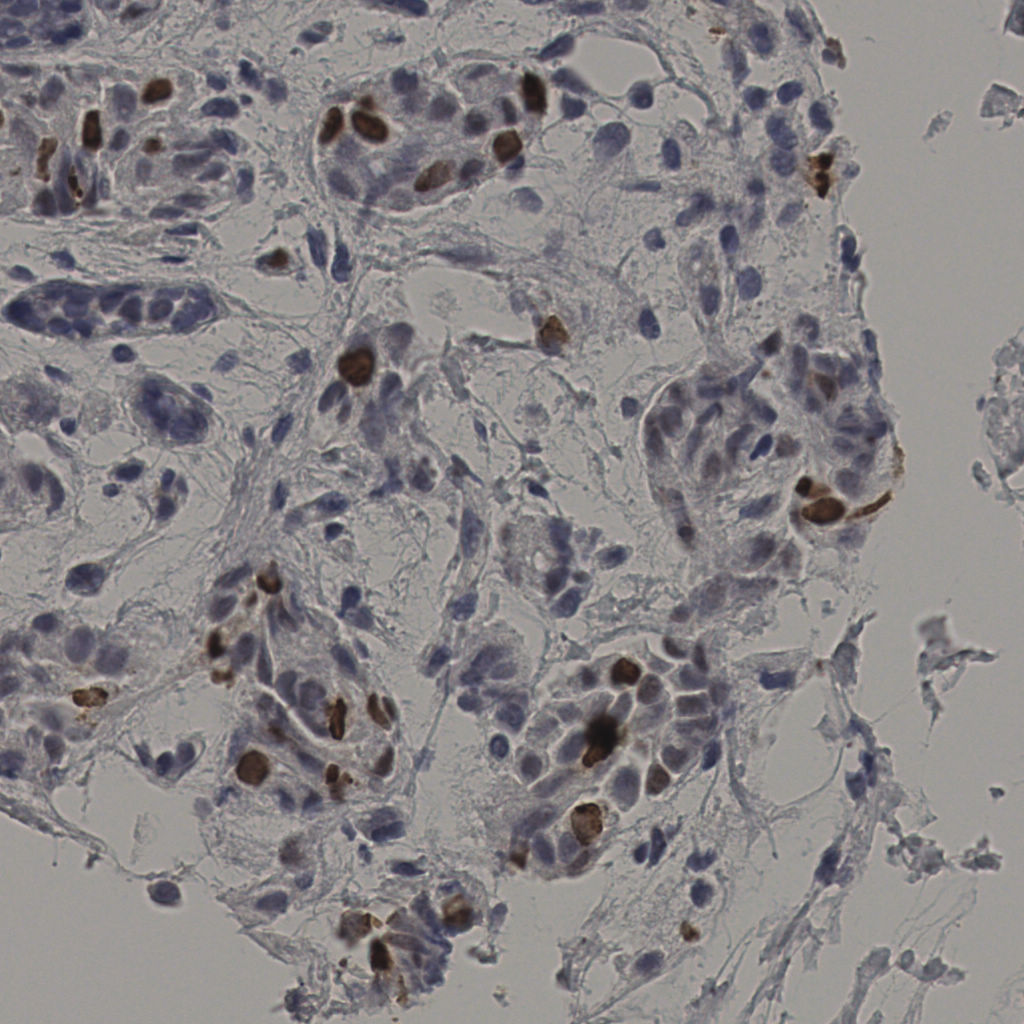

5.31%

Ki67 指数

阴 19502

阳 1093

缩略图

标记后

标记前